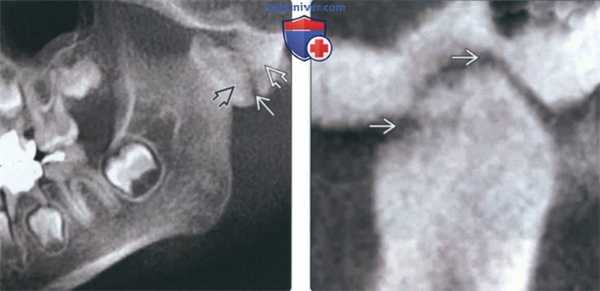

(Слева) На КЛКТ (объемный рендеринг) у подростка с пост-травматическим анкилозом определяется деформация и ремоделирование мыщелка и суставной ямки. Обратите внимание на патологически удлиненный венечный отросток (вследствие гиперплазии), расположенный выше верхнего края скуловой дуги.

(Справа) На косой сагиттальной КЛКТ левой ветви нижней челюсти определяется тонкое линейное просветление между височным и нижнечелюстным компонентом сустава, наличие которого означает фиброзное, а не костное слияние.